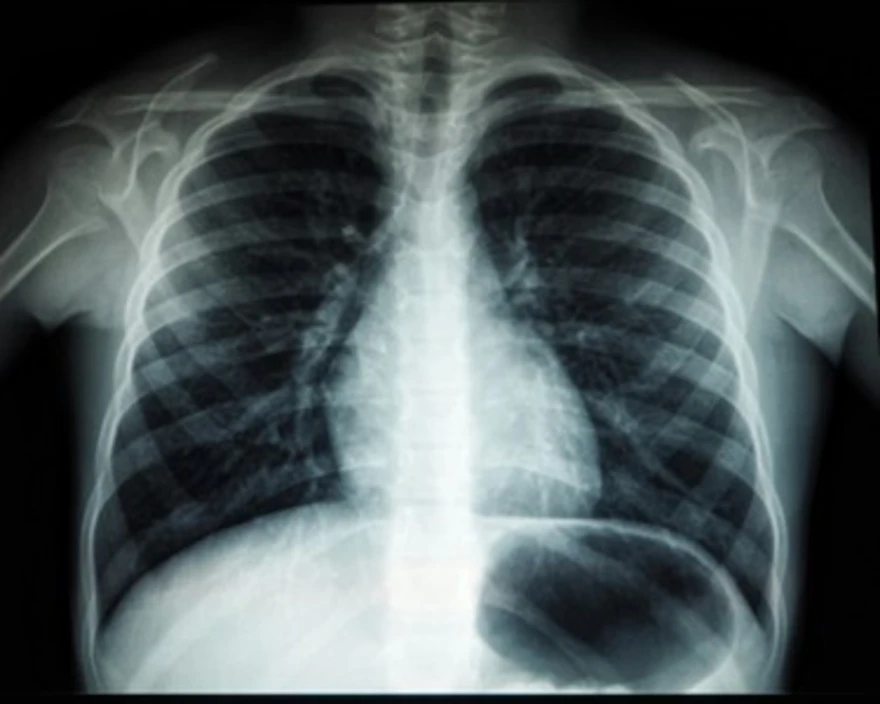

World Radiography Day is celebrated to recognise the discovery of X-rays and the significant contributions of radiographers and radiologic technologists. It raises awareness about the importance of safe imaging practices and the role of diagnostic imaging in improving patient outcomes. The day reminds us that behind every accurate diagnosis is a skilled professional ensuring images are captured with precision, care, and minimal exposure to radiation.

The World Radiography Day 2025 theme, “Empowering Healthcare through Imaging Excellence,” highlights the vital role of medical imaging professionals in enhancing diagnosis, treatment, and patient care. Radiography forms the backbone of modern healthcare, bridging technology and human expertise to detect diseases early and guide precise interventions.

This year’s theme aims to raise awareness about the vital role of radiographic imaging and therapy in diagnosing and treating patients while ensuring minimal radiation exposure to enhance patient safety and care quality.

Radiography forms the backbone of modern diagnostics. Its importance lies in its ability to:

- Detect diseases and abnormalities early, including fractures, tumours, and infections.

- Guide treatment planning in surgeries, cancer therapy, and orthopaedics.

- Monitor patient recovery and the effectiveness of medical interventions.

- Support emergency care by identifying internal injuries swiftly.

- Contribute to medical research, preventive screening, and precision medicine.

Radiography acts as the foundation of multidisciplinary healthcare. Orthopaedic surgeons depend on X-rays for fracture alignment, cardiologists rely on CT angiography for heart health, and oncologists use MRI and PET scans to detect and monitor cancer. Even during pregnancy, ultrasound imaging helps assess foetal growth and maternal health. These applications demonstrate how radiography supports nearly every branch of modern medicine.